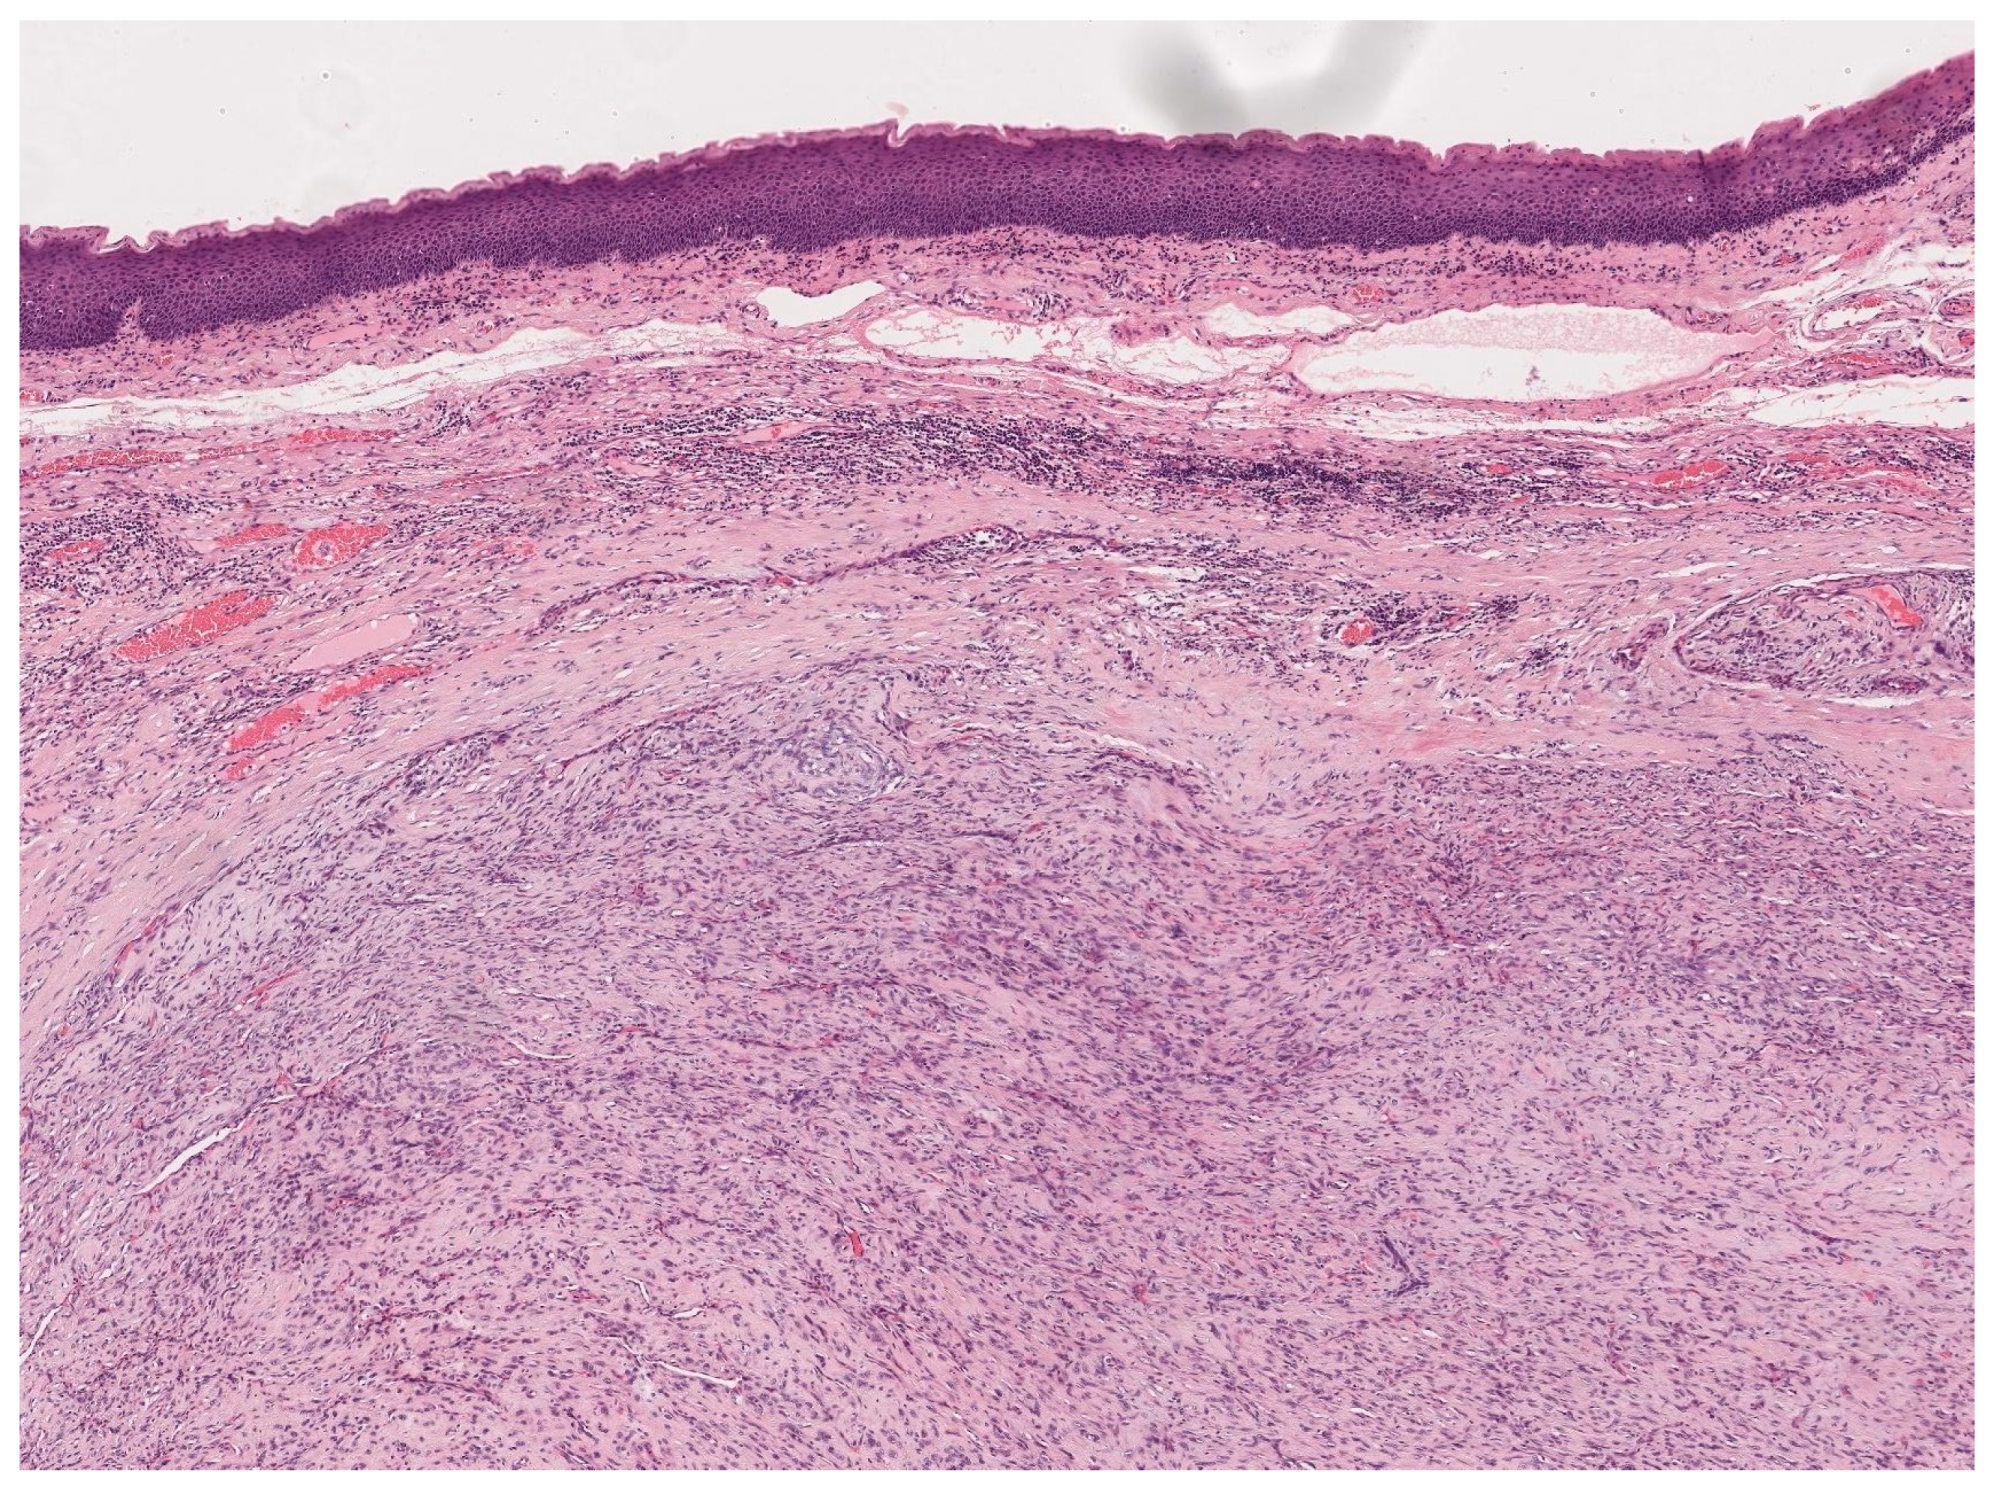

3.8. Malignant Melanoma